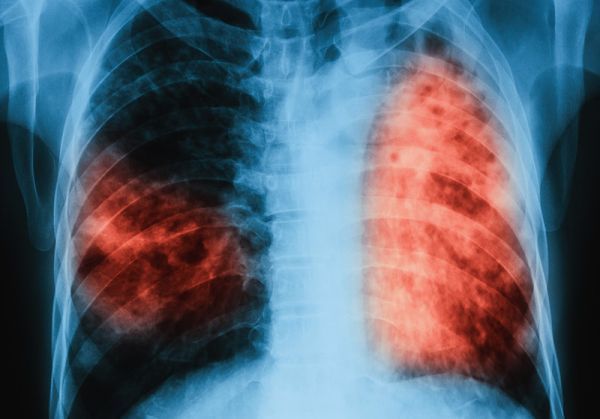

Хроничната обструктивна белодробна болест (ХОББ) е заболяване с все по—нарастваща социална значимост и според прогнозата на СЗО се очаква до 2030 г.да се превърне в третата водеща причина за смърт в световен мащаб. По официална статистика на Министерството на здравеопазването от 2018 г. между 5 и 10% от българите са с ХОББ, а едва 75 000 човека се лекуват. По неофициални данни броят на заболелите в страната е не по-малко от 500 000 души. Статистика на Европейското респираторно дружество сочи, че в Европа всяка година от ХОББ умират 300 000 души. Тези данни бяха представени по време на Национална пулмологична среща на тема “Персоналният подход в лечението на ХОББ: оптимизиране на терапията спрямо нуждите на пациента“, която се проведе в София с участието на повече от 200 пурмолози от цялата страна, както и на гост-лектори от чужбина.

Специалистите смятат, че честотата на ХОББ у нас е значително над средната за Европа и обхваща над 10% от населението над 40-годишна възраст. Причини за това са фактори като масовото активно и пасивно тютюнопушенe, замърсяването на въздуха, наличието на прах, въглероден диоксид, влага в затворените помещения и генетична предразположеност, които увреждат в значителна степен белодробната функция.